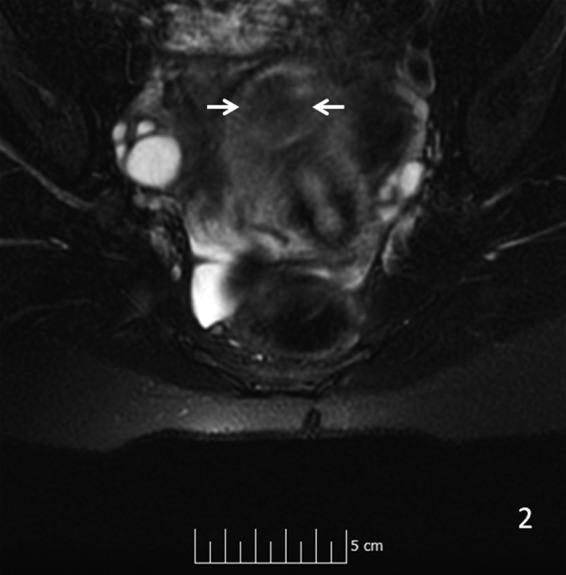

Adenomatoid uterine tumors are rare, and their appearance on medical imaging modalities is not well established. We present a case of an adenomatoid uterine tumor reviewing a unique sonographic presentation, magnetic resonance imaging (MRI), gross surgical appearance of the tumor, and microscopic pathology images. A 29-year-old gravida 0 Caucasian woman presented with dysmenorrhea, menorrhagia, and desire to conceive. Transvaginal ultrasound revealed a 2.7 cm round, well-circumscribed posterior intramural uterine mass. The mass was hyperechoic centrally with a thin hypoechoic rim. Color Doppler imaging revealed a prominent vascular rim around the periphery of the mass as well as central vascularity not typical for a leiomyoma. MRI, with and without intravenous gadolinium, was obtained showing a 2.7 cm posterior fundal mildly enhancing uterine mass suggestive of leiomyoma. The mass had a heterogeneous signal pattern on T2-weighted images, and no fat component was noted within the mass. Repeat transvaginal ultrasound showed interval growth of the mass to 3.5 cm with a lipomatous appearance. Adenomatoid uterine tumors are rare and may be mistaken for uterine leiomyomata. Unique features include sonographic appearance of central hyperechogenicity with a hypoechoic rim and prominent peripheral and central vascularity in conjunction with MRI revealing a heterogeneous signal pattern on T2-weighted images without fat component. Gross surgical appearance reveals a nondiscrete capsule and secretion of mucoid material when the mass is exposed. We present a case of adenomatoid tumor providing sonographic, MRI, surgical, and pathological correlation. The patient subsequently conceived spontaneously and delivered at term by cesarean section. The patient underwent a preoperative evaluation with complete blood count, comprehensive metabolic panel, blood type with antibody screen, and pregnancy test. She underwent laparoscopic excision with robotic assistance for removal of the tumor. Grossly, the uterine mass had a very soft consistency atypical for a uterine leiomyoma making dissection more challenging. During dissection the mass diffusely secreted a mucoid material although the capsule was not disrupted. The lesion was excised intact and was removed from the peritoneal cavity in an endocatch bag without internal morcellation. Microscopic examination revealed an adenomatoid tumor.

腺肌瘤样子宫肿瘤较为罕见,其在医学影像检查中的表现尚未完全明确。我们报告一例腺肌瘤样子宫肿瘤,回顾其独特的超声表现、磁共振成像(MRI)、肿瘤的大体手术外观及微观病理图像。一名29岁未孕的白人女性,因痛经、月经过多及有生育意愿前来就诊。经阴道超声检查发现一个2.7厘米圆形、边界清晰的子宫肌壁间后壁肿物。肿物中央呈高回声,周边有一薄层低回声边缘。彩色多普勒成像显示肿物周边有明显的血管环,且中央有血管分布,这并非平滑肌瘤的典型表现。行MRI检查,静脉注射钆对比剂前后成像显示一个2.7厘米的子宫底部后壁轻度强化肿物,提示为平滑肌瘤。该肿物在T2加权图像上信号不均匀,且肿物内未发现脂肪成分。再次经阴道超声检查显示肿物增大至3.5厘米,呈脂肪瘤样外观。腺肌瘤样子宫肿瘤较为罕见,可能被误诊为子宫平滑肌瘤。其独特特征包括超声表现为中央高回声、周边低回声边缘及明显的周边和中央血管分布,同时MRI显示T2加权图像上信号不均匀且无脂肪成分。大体手术外观显示肿物无明显包膜,肿物暴露时可见黏液样物质分泌。我们报告一例腺肌瘤样肿瘤,提供超声、MRI、手术及病理的相关性。患者随后自然受孕并足月剖宫产分娩。患者术前进行了全血细胞计数、综合代谢指标检测、血型及抗体筛查和妊娠试验等评估。她在机器人辅助下行腹腔镜肿瘤切除术。大体上,子宫肿物质地非常软,这与子宫平滑肌瘤不同,增加了手术分离的难度。手术分离过程中,肿物弥漫性分泌黏液样物质,尽管包膜未破裂。病变完整切除,装入内套袋从腹腔取出,未进行内部碎解。显微镜检查显示为腺肌瘤样肿瘤。